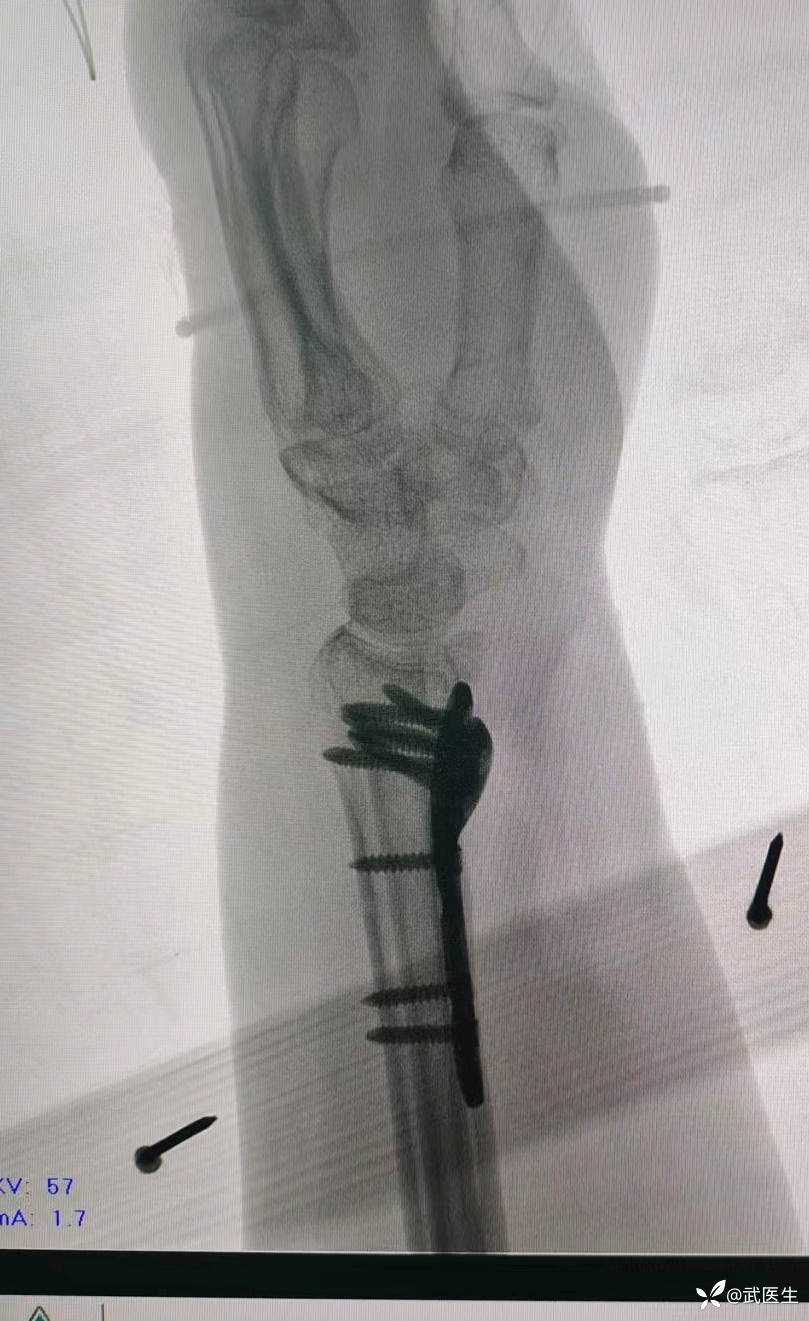

【治疗经过及结果】:入院完善检查,择期安排手术。患者年轻,肱骨外科颈骨折选择保头治疗。择期安排。

术中透视复位良好,术后CT验证一下